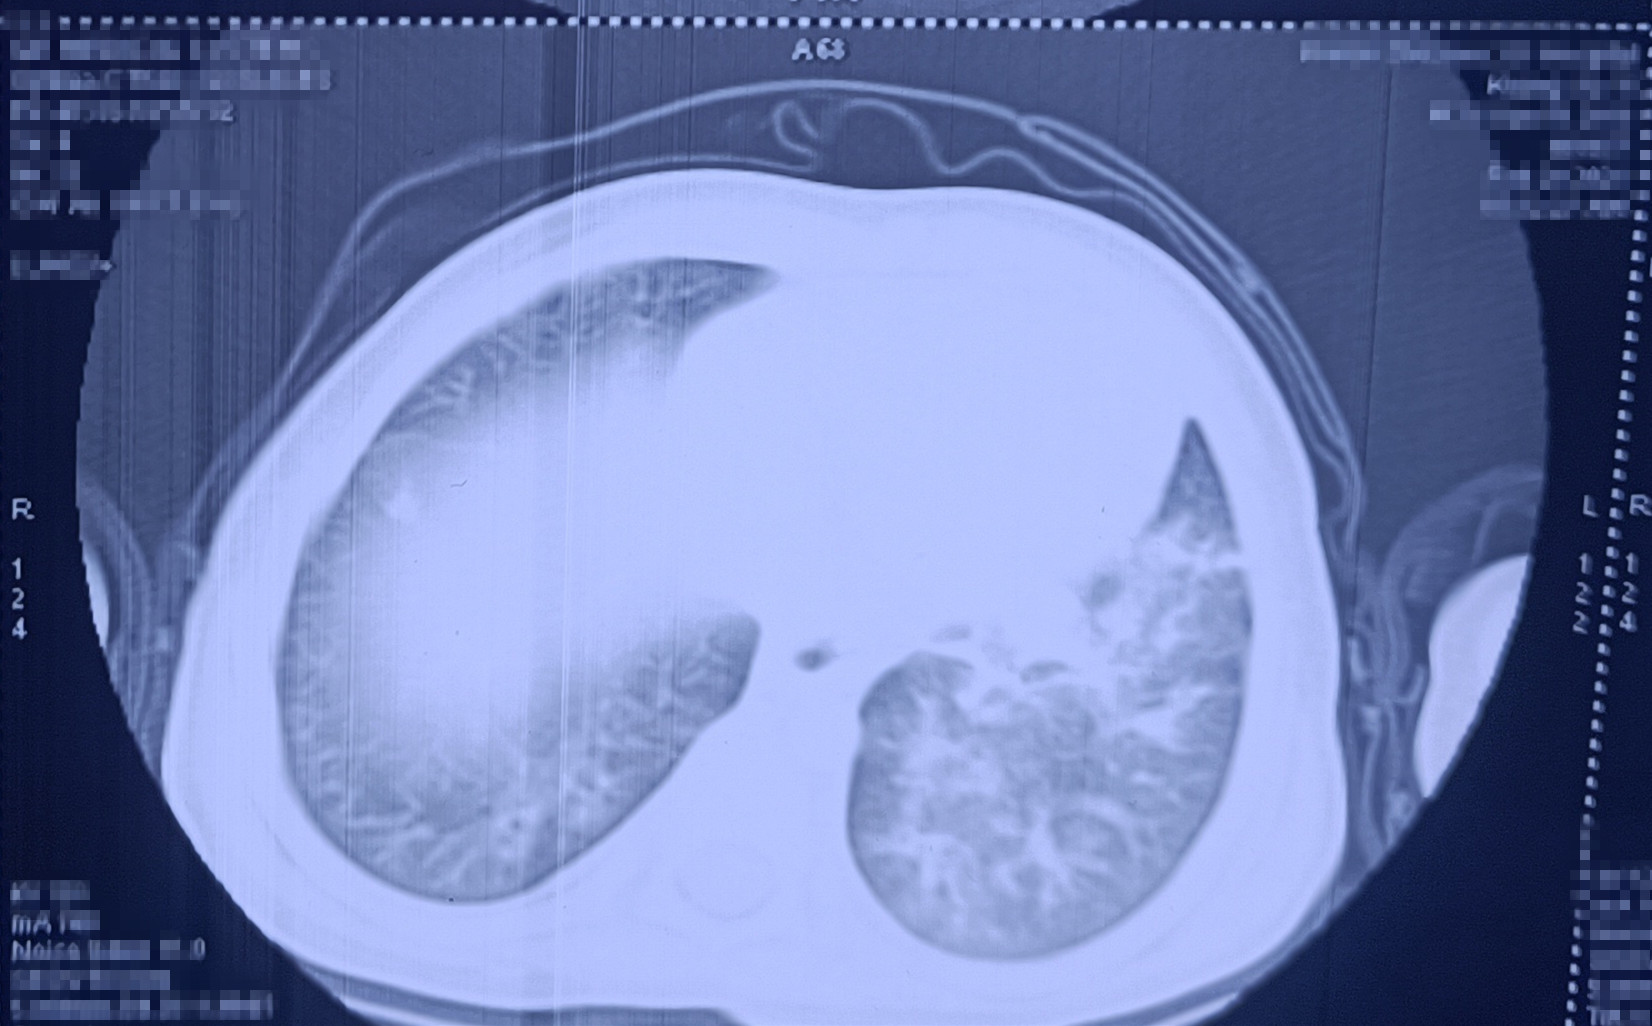

呼吸介入科主任黄寒立即查看明明情况,发现这时的明明发高烧、呼吸急促费力且烦躁不安,结合临床病史及影像资料,考虑溺粪后感染严重,易引发急性负压性肺水肿导致病情进一步恶化,紧急予以床旁行急诊儿童支气管检查、无创呼吸机辅助呼吸等。经过医护人员的紧急救治、积极抗感染等对症支持治疗及精心护理后,孩子终于度过危险期,病情逐渐稳定下来,并于今日顺利出院。